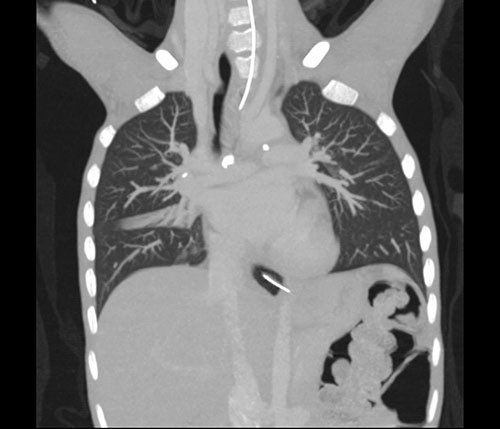

På dag 7 ble det gjort CT thorax, som viste flere forkalkede lymfekjertler i det aortopulmonale vindu og i høyre hilus (fig 1) samt en forkalkning i venstre overlapps basalfelt som kunne representere Gohns fokus, altså et tuberkuløst primærkompleks (fig 2). Man så sentrale sakkulære bronkieektasier, mest i høyre lunge, samt tynne atelektatiske fortetninger langs fissura major i venstre lunge, men ingen infiltrater eller kaverner. Oesophagus var dilatert i hele sin lengde med uttalt trang overgang til ventrikkelen.

Selv om funnene på CT thorax var mest forenlig med tidligere gjennomgått tuberkulose, kunne vi ikke utelukke aktiv sykdom. IGRA-testen var negativ, men det faktum at den viste lav mitogenkontroll, kunne peke i retning av at pasienten hadde nedsatt immunforsvar, noe som var sannsynlig på grunn av den alvorlige underernæringen.